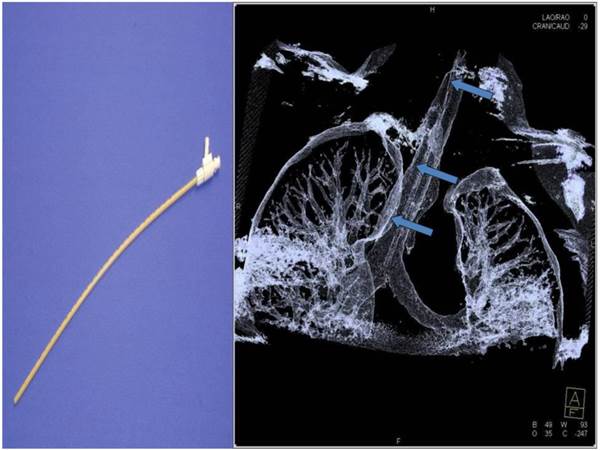

Figure 4

An example of navigation up to a SPN after the 8th segmentation (counted from the main carina).

Figure 5

Jet-catheter inserted in trachea in DynaCT (arrows).